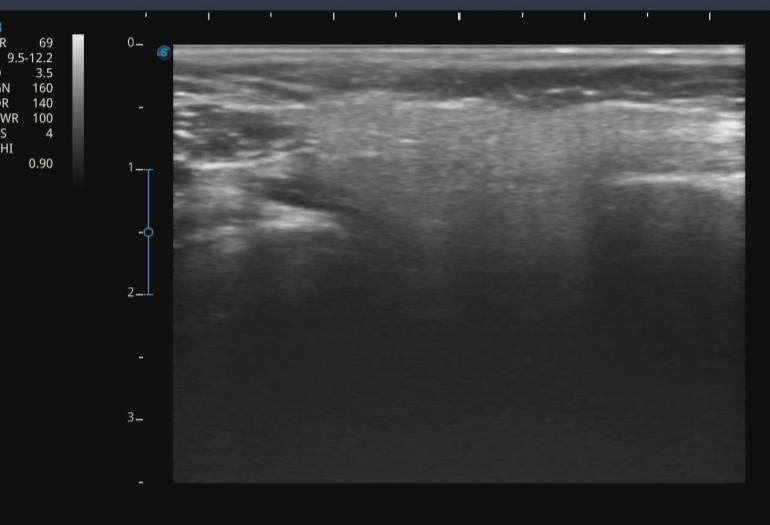

• Ultrasound-guided intramuscolar injection